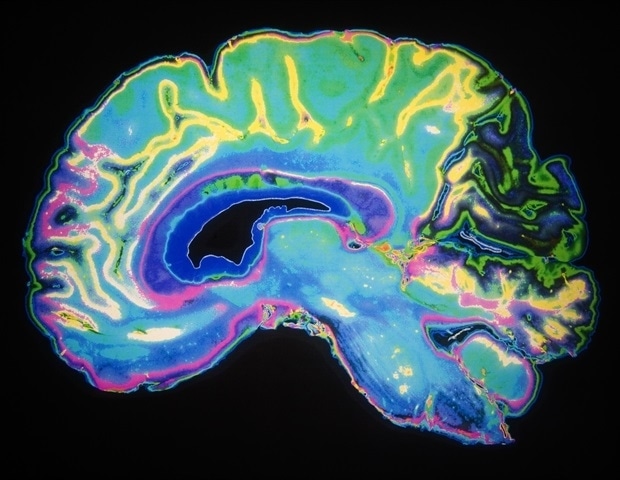

The mind is split into two hemispheres that procedure knowledge in a partly specialised way, but they wish to coordinate continuously. Alternatively, the particular connections that permit this conversation in areas eager about reminiscence, such because the hippocampus, are in large part unknown.

On this paintings, the group recognized this kind of connections: a neuronal projection linking the CA1 area of the fitting hemisphere with the subiculum of the left hemisphere. To do that, the researchers used neuronal tracing ways that permit them to apply the trail of connections between neurons. “This circuit acts as a bridge between the 2 areas and allows the combination of knowledge had to navigate and take note the places of items”, says Noelia Sofía de León Reyes, the primary creator of the learn about.